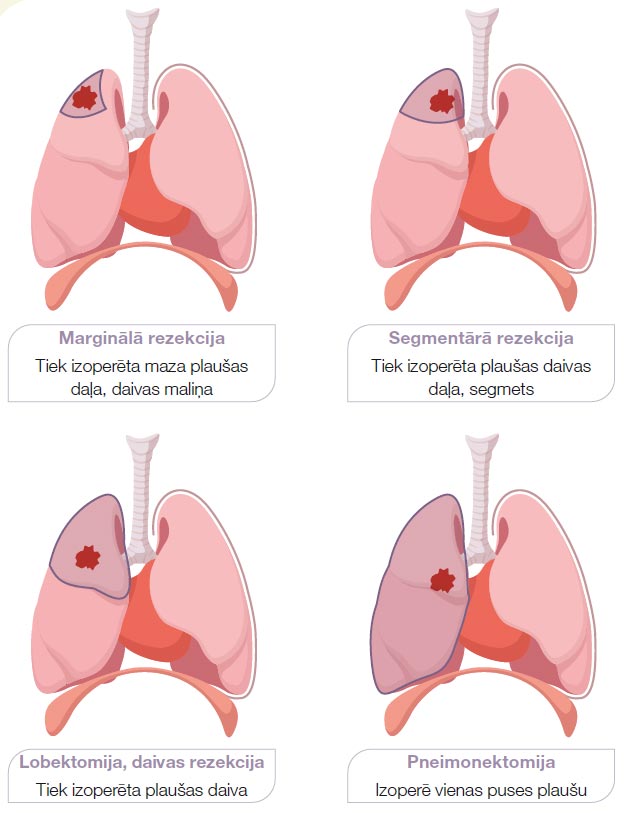

ĶIRURĢISKA ĀRSTĒŠANA

Ķirurģisku ārstēšanu izvēlas, kad vien iespējams, kā potenciāli izārstējošo nesīkšūnu plaušu vēža gadījumā. Operācija ar izārstēšanas mērķi ir iespējama, ja plaušu vēzis ir 0–II stadijā un dažreiz III stadijā. Sīkšūnu plaušu vēža gadījumā operāciju izvēlas reti – simptomu atvieglošanai vai ļoti agrīnās stadijās. Sīkšūnu plaušu vēzis attīstās tuvu lielajiem elpceļiem, sasniedz lielu izmēru un ātri izplatās, tāpēc pilnībā izoperēt to visbiežāk nav iespējams. Plaušu vēža operācijas tiek veiktas vispārējā narkozē. Operāciju veic torakālais ķirurgs.

Ķirurģisku ārstēšanu izvēlas, kad vien iespējams, kā potenciāli izārstējošo nesīkšūnu plaušu vēža gadījumā. Operācija ar izārstēšanas mērķi ir iespējama, ja plaušu vēzis ir 0–II stadijā un dažreiz III stadijā. Sīkšūnu plaušu vēža gadījumā operāciju izvēlas reti – simptomu atvieglošanai vai ļoti agrīnās stadijās. Sīkšūnu plaušu vēzis attīstās tuvu lielajiem elpceļiem, sasniedz lielu izmēru un ātri izplatās, tāpēc pilnībā izoperēt to visbiežāk nav iespējams. Plaušu vēža operācijas tiek veiktas vispārējā narkozē. Operāciju veic torakālais ķirurgs.

Plaušu operācija ir liela ķirurģiska manipulācija, kas ir saistīta ar zināmiem riskiem un iespējamām komplikācijām. Riski pieaug līdz ar operācijas apjomu un iekļauj reakciju uz anestēziju, asiņošanu, dziļo vēnu trombozi, brūču infekcijas, plaušu iekaisumu.

Atkopšanās periods pēc plaušu operācijas ilgst nedēļas līdz mēnešus. Ja operācija tiek veikta ar lielu griezienu krūškurvja sienā, tad kādu laiku pēc operācijas var būt nepieciešama pretsāpju terapija, jo operācijas laikā tiek atbīdītas ribas. Ja plaušu stāvoklis pacientam pirms operācijas ir labs, nav hronisku plaušu slimību, tad pat pēc visas plaušas izņemšanas ar laiku pacients var atgriezties pie pilnīgi normāla ikdienas aktivitātes līmeņa un darbaspējām. Savukārt, ja ir hroniskas plaušu slimības kā emfizēma, hronisks smēķētāja bronhīts, tad pēc operācijas var parādīties nepārejošs elpas trūkums pie fiziskās slodzes. Operācijas riskus izvērtē, balstoties uz pacienta vispārējo stāvokli, blakusslimībām, asins analīzēm un pirms operācijas veiktiem elpošanas funkcijas testiem. Sekojoši torakālais ķirurgs pieņem lēmumu par operācijas apjomu un iespējām.